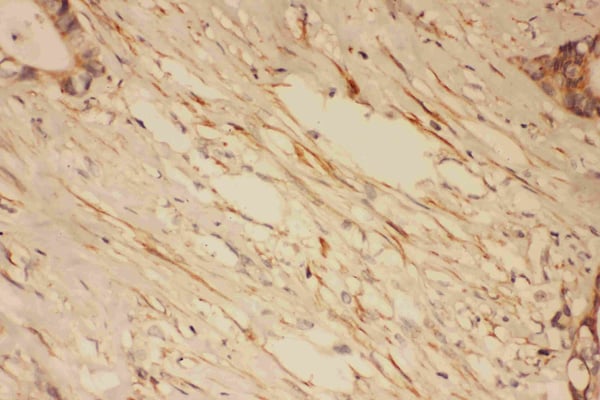

IHC (Immunohistochemistry)

(Anti-PSD95 antibody, AAA45684, IHC(P)IHC(P): Human Intestinal Cancer Tissue)